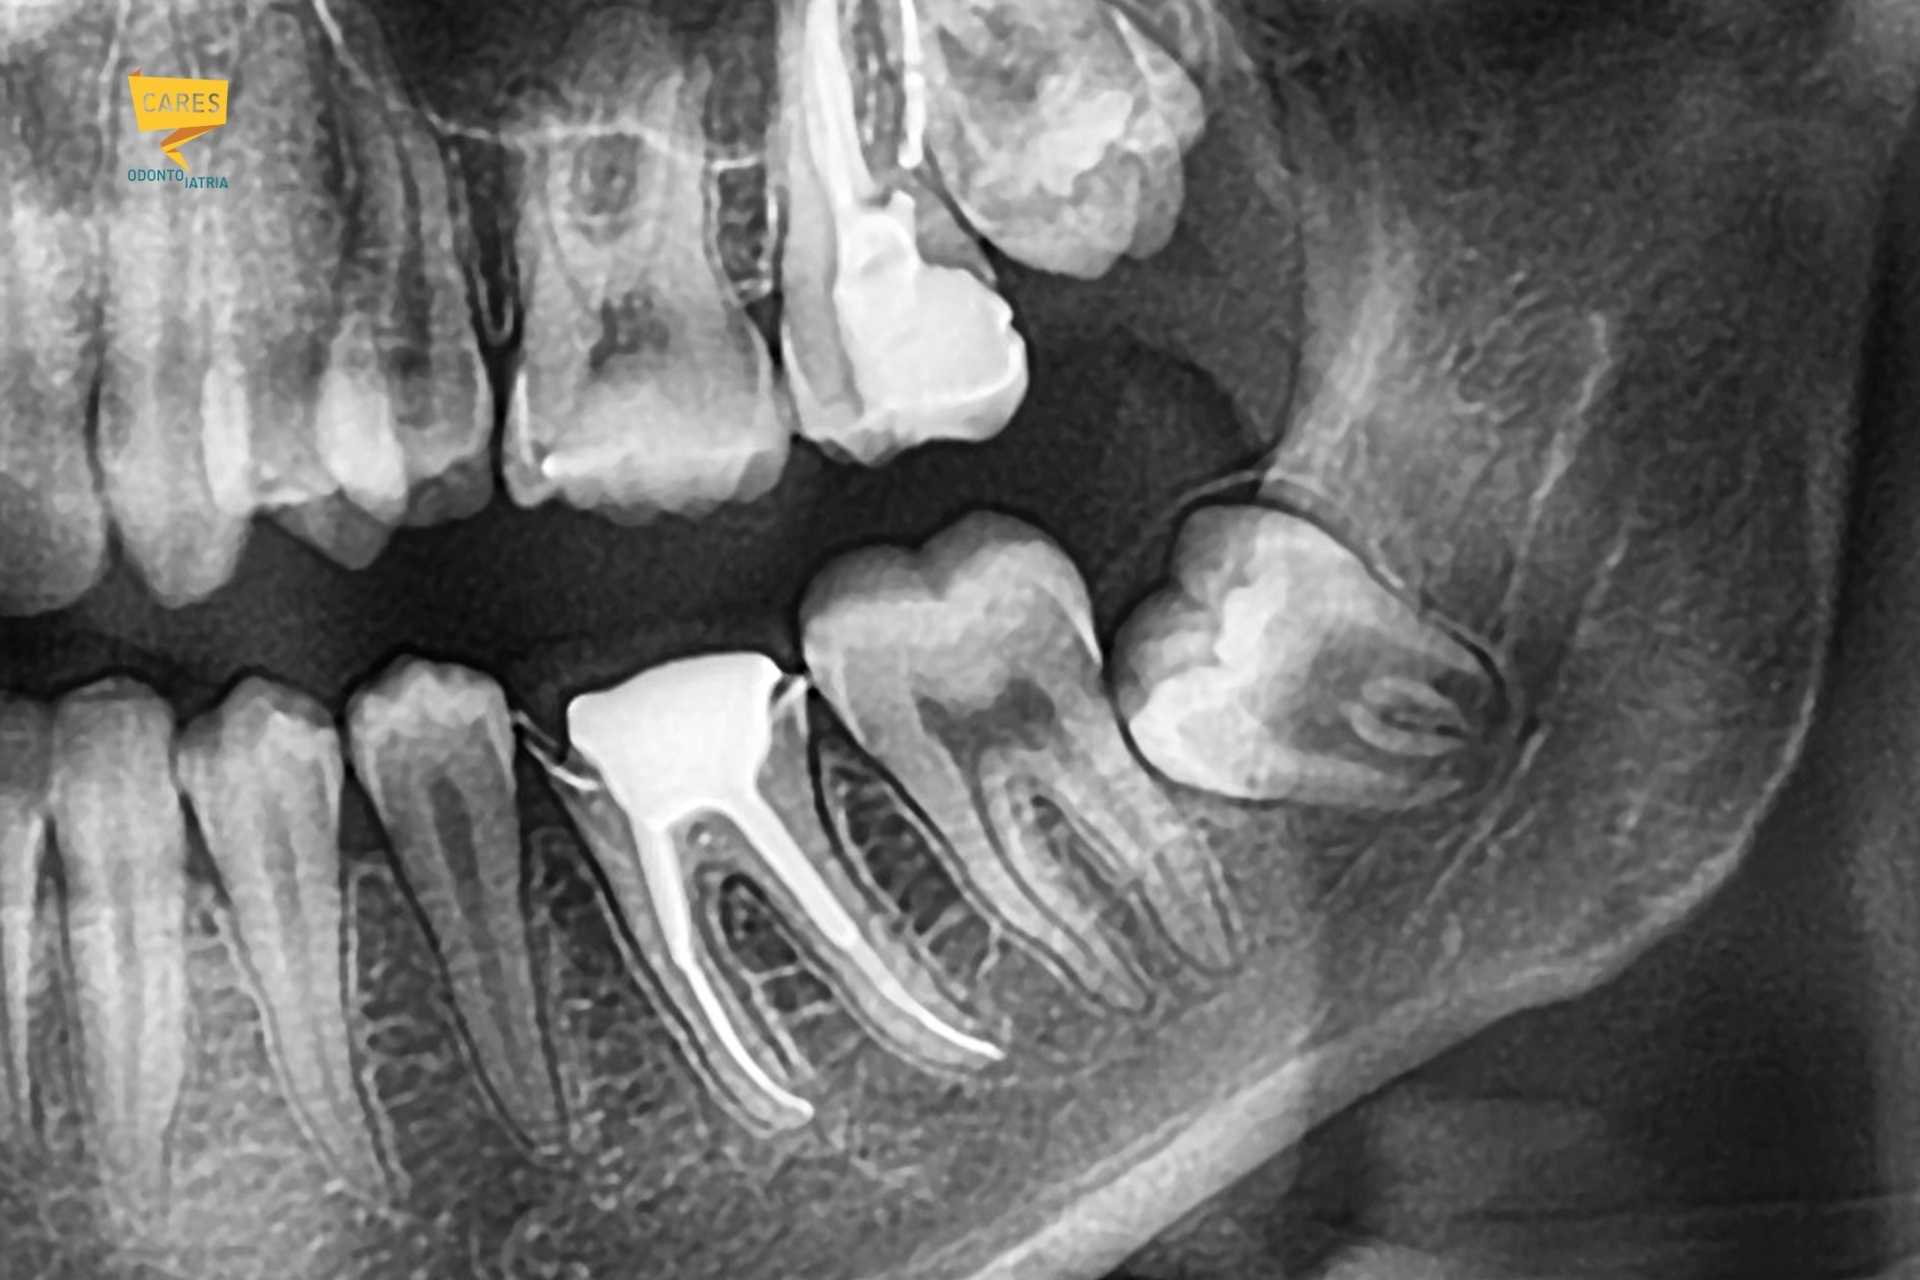

Radiografia dentale che mostra un dente del giudizio inferiore incluso in posizione orizzontale vicino al secondo molare e al nervo mandibolare.

Inclusione/impattamento: disodontiasi degli ottavi

Quando il terzo molare non riesce a erompere (o erompe in posizione non funzionale) si parla di “inclusione” o “impattamento”; nel linguaggio clinico e divulgativo si incontra la formula disodontiasi degli ottavi. Questo quadro può restare silente a lungo oppure favorire carie del secondo molare, tasche parodontali distali e infiammazioni ricorrenti. Questo è lo scenario tipico in cui il dente del giudizio è spesso da estrarre per evitare un peggioramente della qualità della vita o dello stato di salute della bocca.

Vicino ai nervi: non è un dettaglio

Per i terzi molari inferiori, il tema cruciale è il rapporto con il canale mandibolare e il nervo alveolare inferiore. La rimozione può “disturbare” i nervi vicini causando formicolio o intorpidimento di labbro e mento (nervo alveolare inferiore) o, meno spesso, alterazioni della sensibilità della lingua (nervo linguale).

Le linee guida internazionali indicano la radiografia panoramica come esame di primo livello quando l’intervento è in valutazione: serve a vedere la posizione, l’inclinazione, la forma delle radici ed una idea del rapporto che possono avere con il canale del nervo alveolare inferiore.

La CBCT (Cone Beam) è una tomografia 3D a campo limitato. È utile quando la panoramica mostra segni radiologici di possibile rapporto stretto con il canale mandibolare. In questi casi la CBCT aiuta a chiarire se esiste una parete ossea tra dente e canale e può cambiare strategia per poter risolvere la problematica in totale sicurezza.